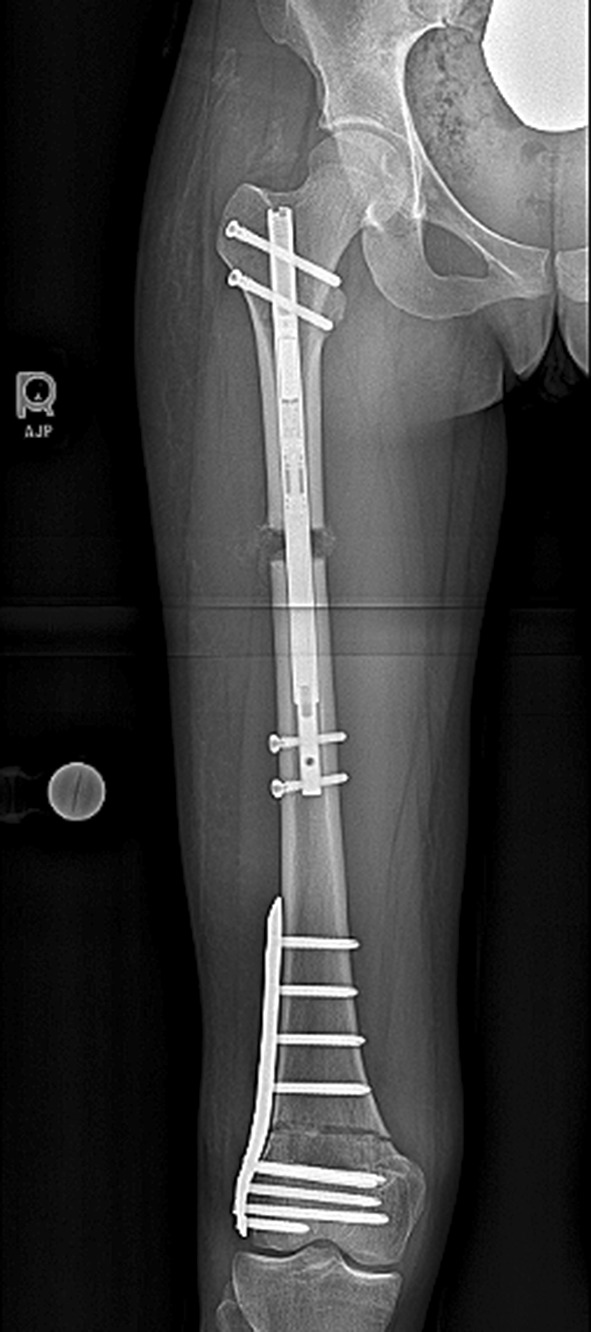

Fig. 5.

This post-operative radiograph demonstrates the entire construct including the piriformis entry ILN and the distal plate. This needs to be planned well to ensure the proper nail length and osteotomy location are selected so that the nail is long enough to control the lengthening bone but short enough to not interfere with the plate. The concern about a stress riser between the nail and the plate has not been an issue in this young adult population